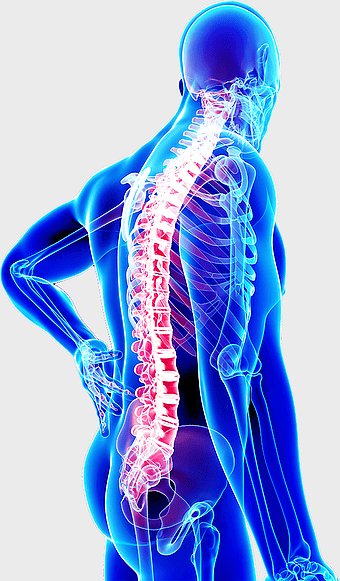

spine skeleton illustration, orthopedic surgery, musculoskeletal disorder, human body anatomy, skeletal health, medical imaging, spine health analysis -